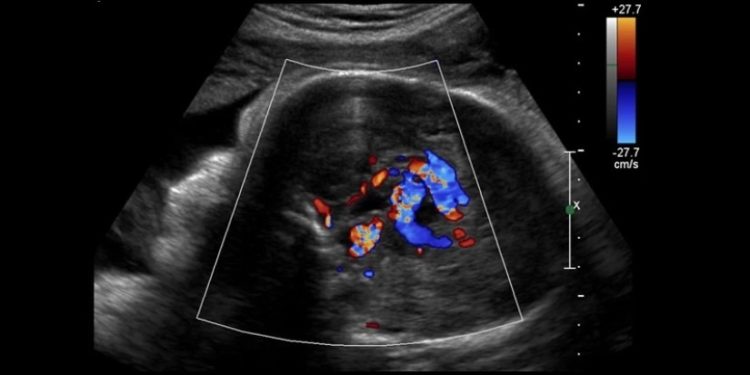

იშვიათი პრენატალური (დაბადებამდელი) მდგომარეობის სამკურნალოდ, ბოსტონის ბავშვთა ჰოსპიტლისა და Brigham and Women’s ჰოსპიტლის ქირურგებმა მეთოდი, სახელად ემბოლიზაცია გამოიყენეს. დაავადებას გალენის ვენის მალფორმაციას (VOGM) უწოდებენ და წარმოადგენს სისხლძარღვთა ანომალიას, რომლის გამოც, ბავშვის დაბადების შემდეგ, მისი თავის ტვინის გარკვეულ ნაწილში სისხლი სახიფათოდ ჩქარა მოძრაობს. პროცედურის წარმატება აჩენს იმედს, რომ ამ დაავადების მკურნალობა იქამდე იქნება შესაძლებელი, ვიდრე გართულებათა რისკი გაიზრდება.

„მიმდინარე ცდაში, გალენის ვენის მალფორმაციის დაბადებამდევე სამკურნალოდ ვიყენებთ ულტრაბგერით მართვად საშვილოსნოსშიდა ემბოლიზაციას. მკურნალობის პირველ შემთხვევაში, აღფრთოვანებული დავრჩით პათოლოგიის აგრესიული შემცირებით“, – ამბობს ბოსტონის ბავშვთა ჰოსპიტლისა და ჰარვარდის სამედიცინო სკოლის ნეიროინტერვენციული რადიოლოგი დარენ ორბახი.